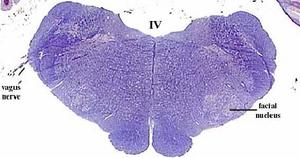

secciones transversales a diferentes niveles del tronco del encéfalo mostrando la localización de los núcleos neuronales aferentes de los nervios craneales

AFERENTES:

Somatoaferentes:

generales (GSA): boca y cara

-especiales (SSA): sentido de la visión y oído

Visceroaferentes:

- generales (GVA): recogen sensación de faringe y laringe

-especiales (SVA): sentido del gusto y del olfato